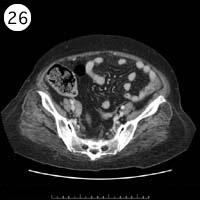

57歳 女性

単純CT

造影CT